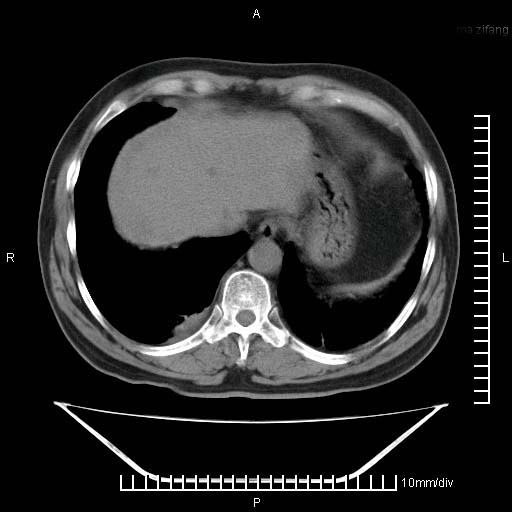

标题: CT25082:肝脏增强:男性,70岁 [打印本页]

标题: CT25082:肝脏增强:男性,70岁

患者以心脏疾病收住院,腹部无明显症状,b超查肝脏有占位。

增强效果不理想。考虑转移,胆囊壁明显增厚,不排除胆囊癌肝转移。

牛眼征,中心坏死无强化,外缘强化,最外缘又见低密度,考虑转移,与脓肿鉴别

考虑右肺下叶周围癌肝转移

肝内多发转移瘤,右下肺炎症并少量胸水。胃壁增厚建议胃镜,胰尾部“病变”为肠管。

1)肝脏多发性转移瘤(不排除胰尾癌转移所致可能)。2)腹水。3)右侧少量胸腔积液。

ct25082 结果:转移瘤

外院mr结果:胰尾恶性占位。